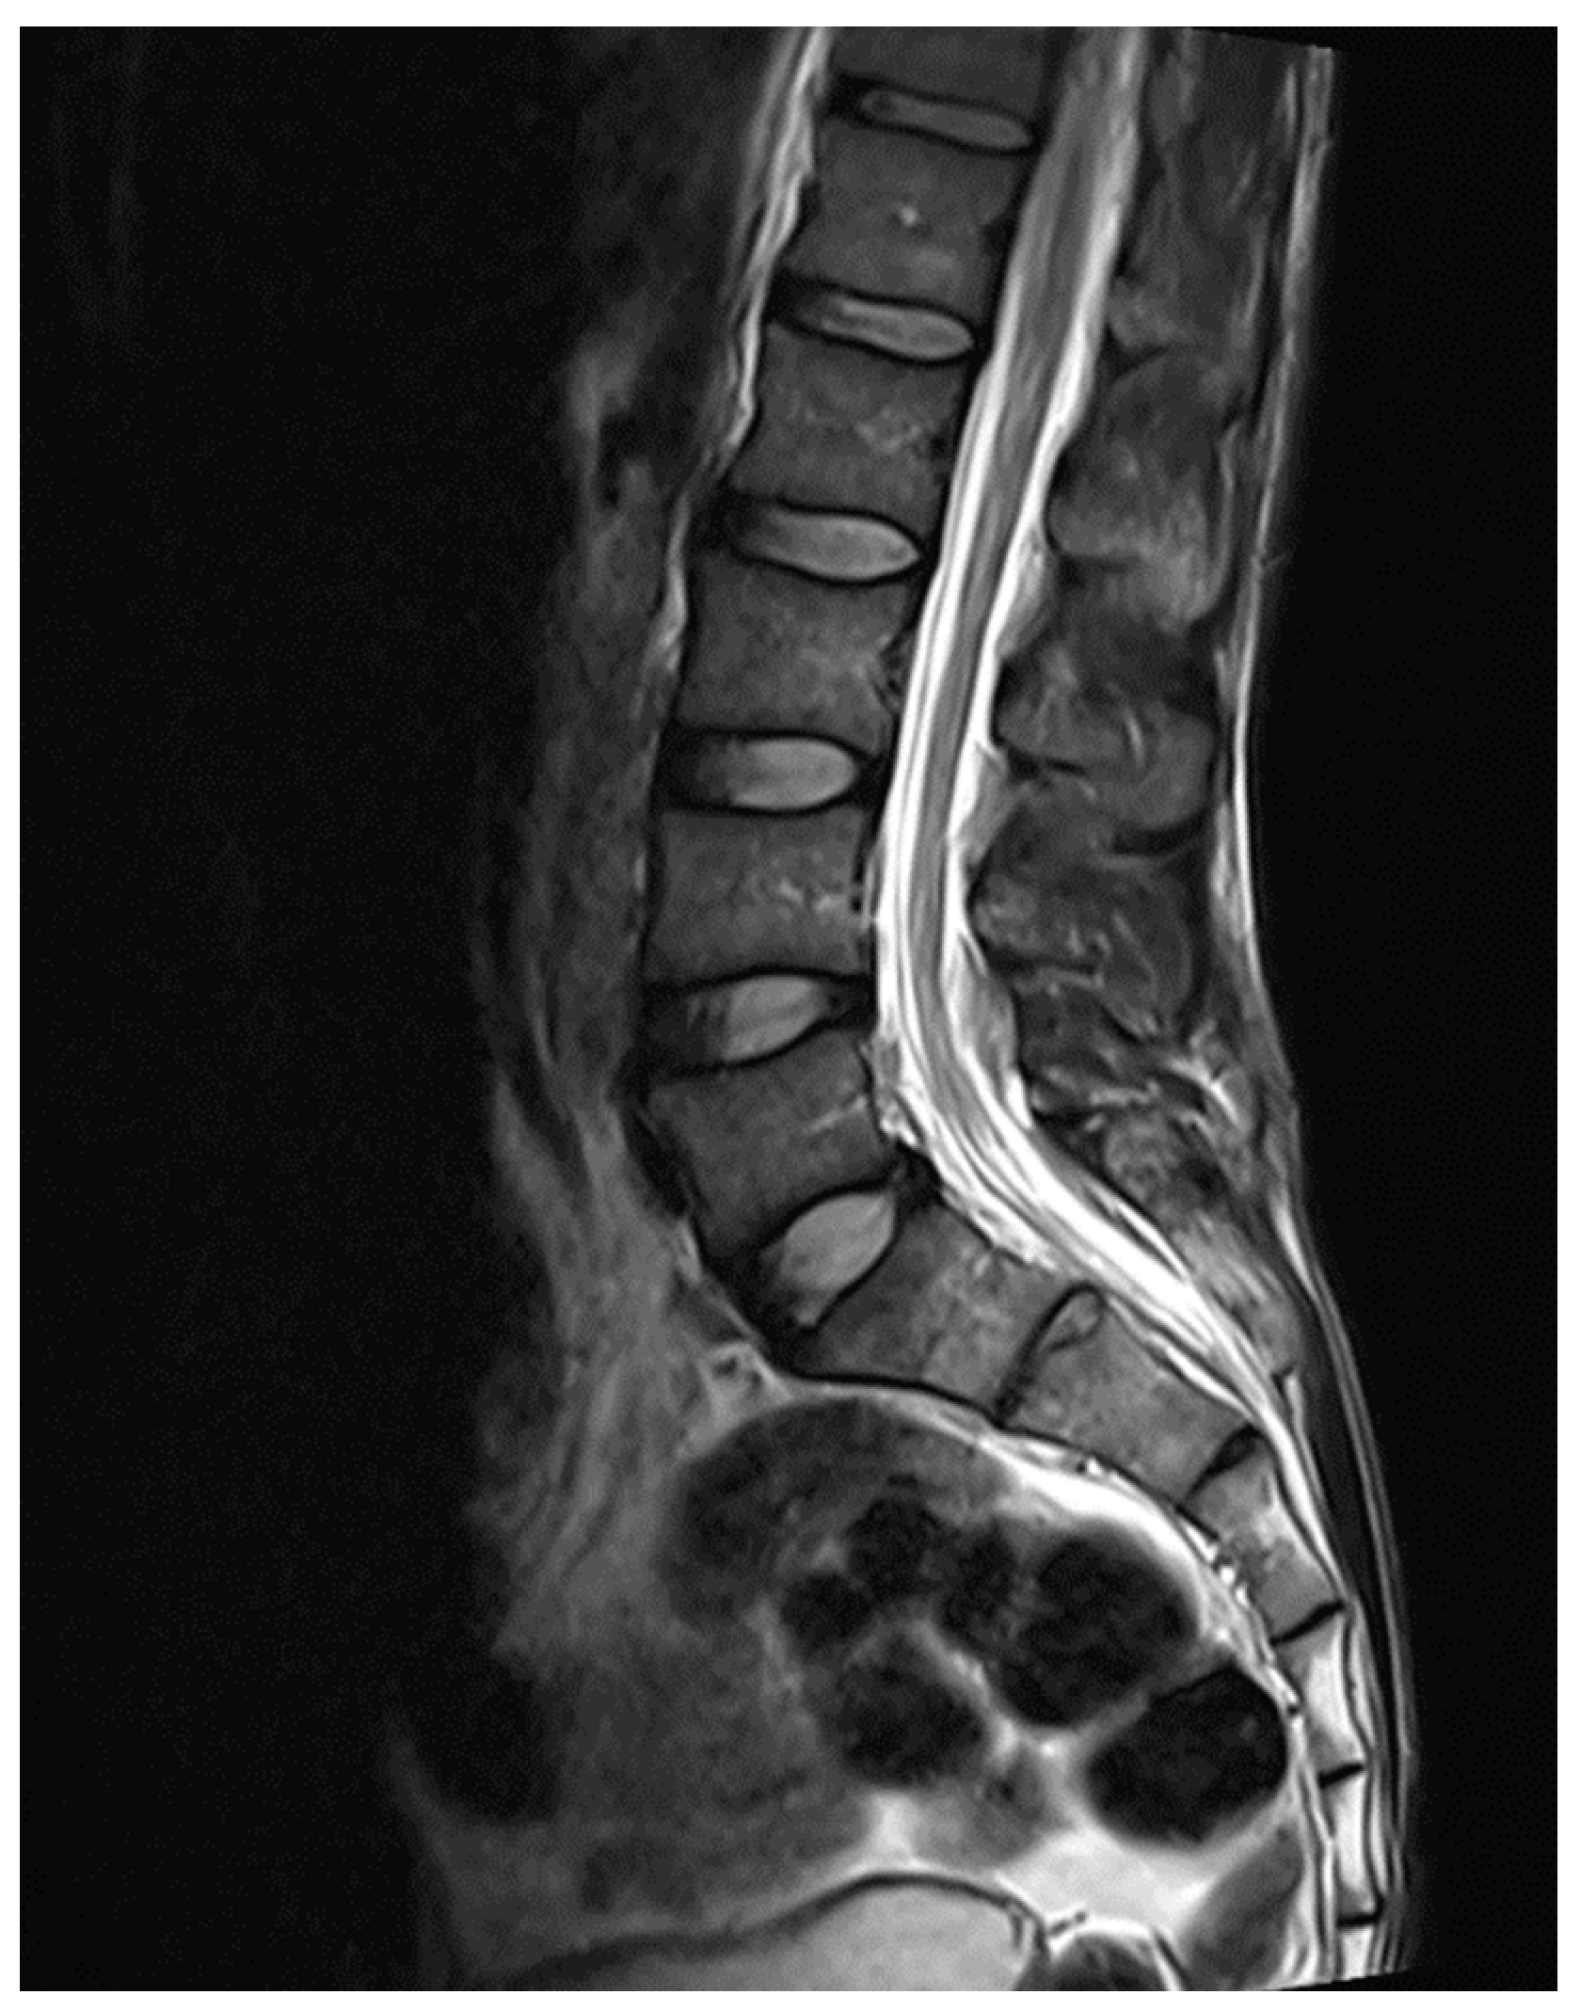

Figure 6. MRI spine L5-S1 level.

MRI whole spine screening showed early disc desiccation at upper cervical vertebral levels. Haemangioma was noted in the body of the D2 vertebra. C3-C4 level showed disc osteophytes complex causing indentation over anterior thecal sac without causing significant nerve root compression. Repeated MRI Spine showed an abutment over the right exiting nerve root at the above-mentioned level. L5-S1 level showed diffuse disc bulge causing bilateral lateral recess stenosis, neural foraminal narrowing and indentation over the anterior thecal sac with resultant abutment over bilateral exiting nerve roots. Above-stated findings give evidence of demyelinating Balo’s Concentric Sclerosis.